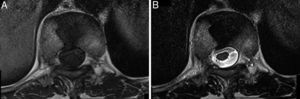

Radiografía lateral de columna dorsal mostrando un aparente aplastamiento vertebral cuneiforme anterior de D10 (A, flecha). La RM mostraba en los cortes sagitales de la secuencia potenciada en T1 un acuñamiento anterior similar al observado en la radiografía (B, flecha), pero en los cortes coronales se evidenció que en realidad correspondía a un defecto de fusión del cuerpo vertebral, que originaba la presencia de 2 hemivértebras, la derecha ligeramente menor que la izquierda, con la apariencia típica de «vértebra en mariposa» (C, cabezas de flechas).

La vértebra en mariposa (también conocida como hendidura sagital vertebral, raquisquisis anterior, somatosquisis, o espina bífida anterior1) es una malformación congénita rara producida por el fallo de la fusión de los núcleos de condrificación laterales de la vértebra en desarrollo2,3, secundario a una regresión embriológica incompleta de la notocorda que origina un surco sagital en forma de embudo dentro del cuerpo vertebral, a través del cual se conectan los discos vertebrales adyacentes4. Este defecto ocurre entre la 3.ª a 6.ª semana de gestación2,3 y se localiza con mayor frecuencia a nivel lumbar5–7. Se asocia a otras alteraciones congénitas como la hipo/aplasia mülleriana y los síndromes de Jarcho-Levin, Pfeiffer, Crouzon, Alagille y Kallmann, aunque también puede ocurrir de forma aislada1,2,7,8. Los pacientes habitualmente son asintomáticos y esta malformación suele detectarse de forma incidental, pero puede alterar la biomecánica de la columna causando dolor lumbar atípico o aumentando la posibilidad de herniación discal5–7. En la radiografía lateral muestra una morfología trapezoidal o cuneiforme anterior, por lo que puede confundirse con un aplastamiento vertebral osteoporótico u otras fracturas vertebrales patológicas, incluyendo las traumáticas, infecciosas o metástasicas1,2,7,9. El acuñamiento es causado por hipo/aplasia anterior debido a un déficit congénito de la vascularización3,9. En la radiografía anteroposterior se detecta fácilmente debido a que la vértebra se divide en 2 hemivértebras (habitualmente simétricas, pero pueden ser de tamaño distinto condicionando escoliosis), que lucen como las alas de una mariposa1,2,4, pero esta radiografía no estuvo disponible en nuestro caso. La TC y la RM se recomiendan en casos dudosos o para excluir otras anomalías congénitas asociadas tales como barras vertebrales, vértebras lumbares supernumerarias, espina bífida, diastematomielia o cifoescoliosis6. Recientemente, se ha descrito el uso de la ultrasonografía fetal tridimensional para el diagnóstico prenatal de la vértebra en mariposa10. En conclusión, aunque la vértebra en mariposa es infrecuente, debería tenerse en cuenta en el diagnóstico diferencial del aplastamiento vertebral osteoporótico.